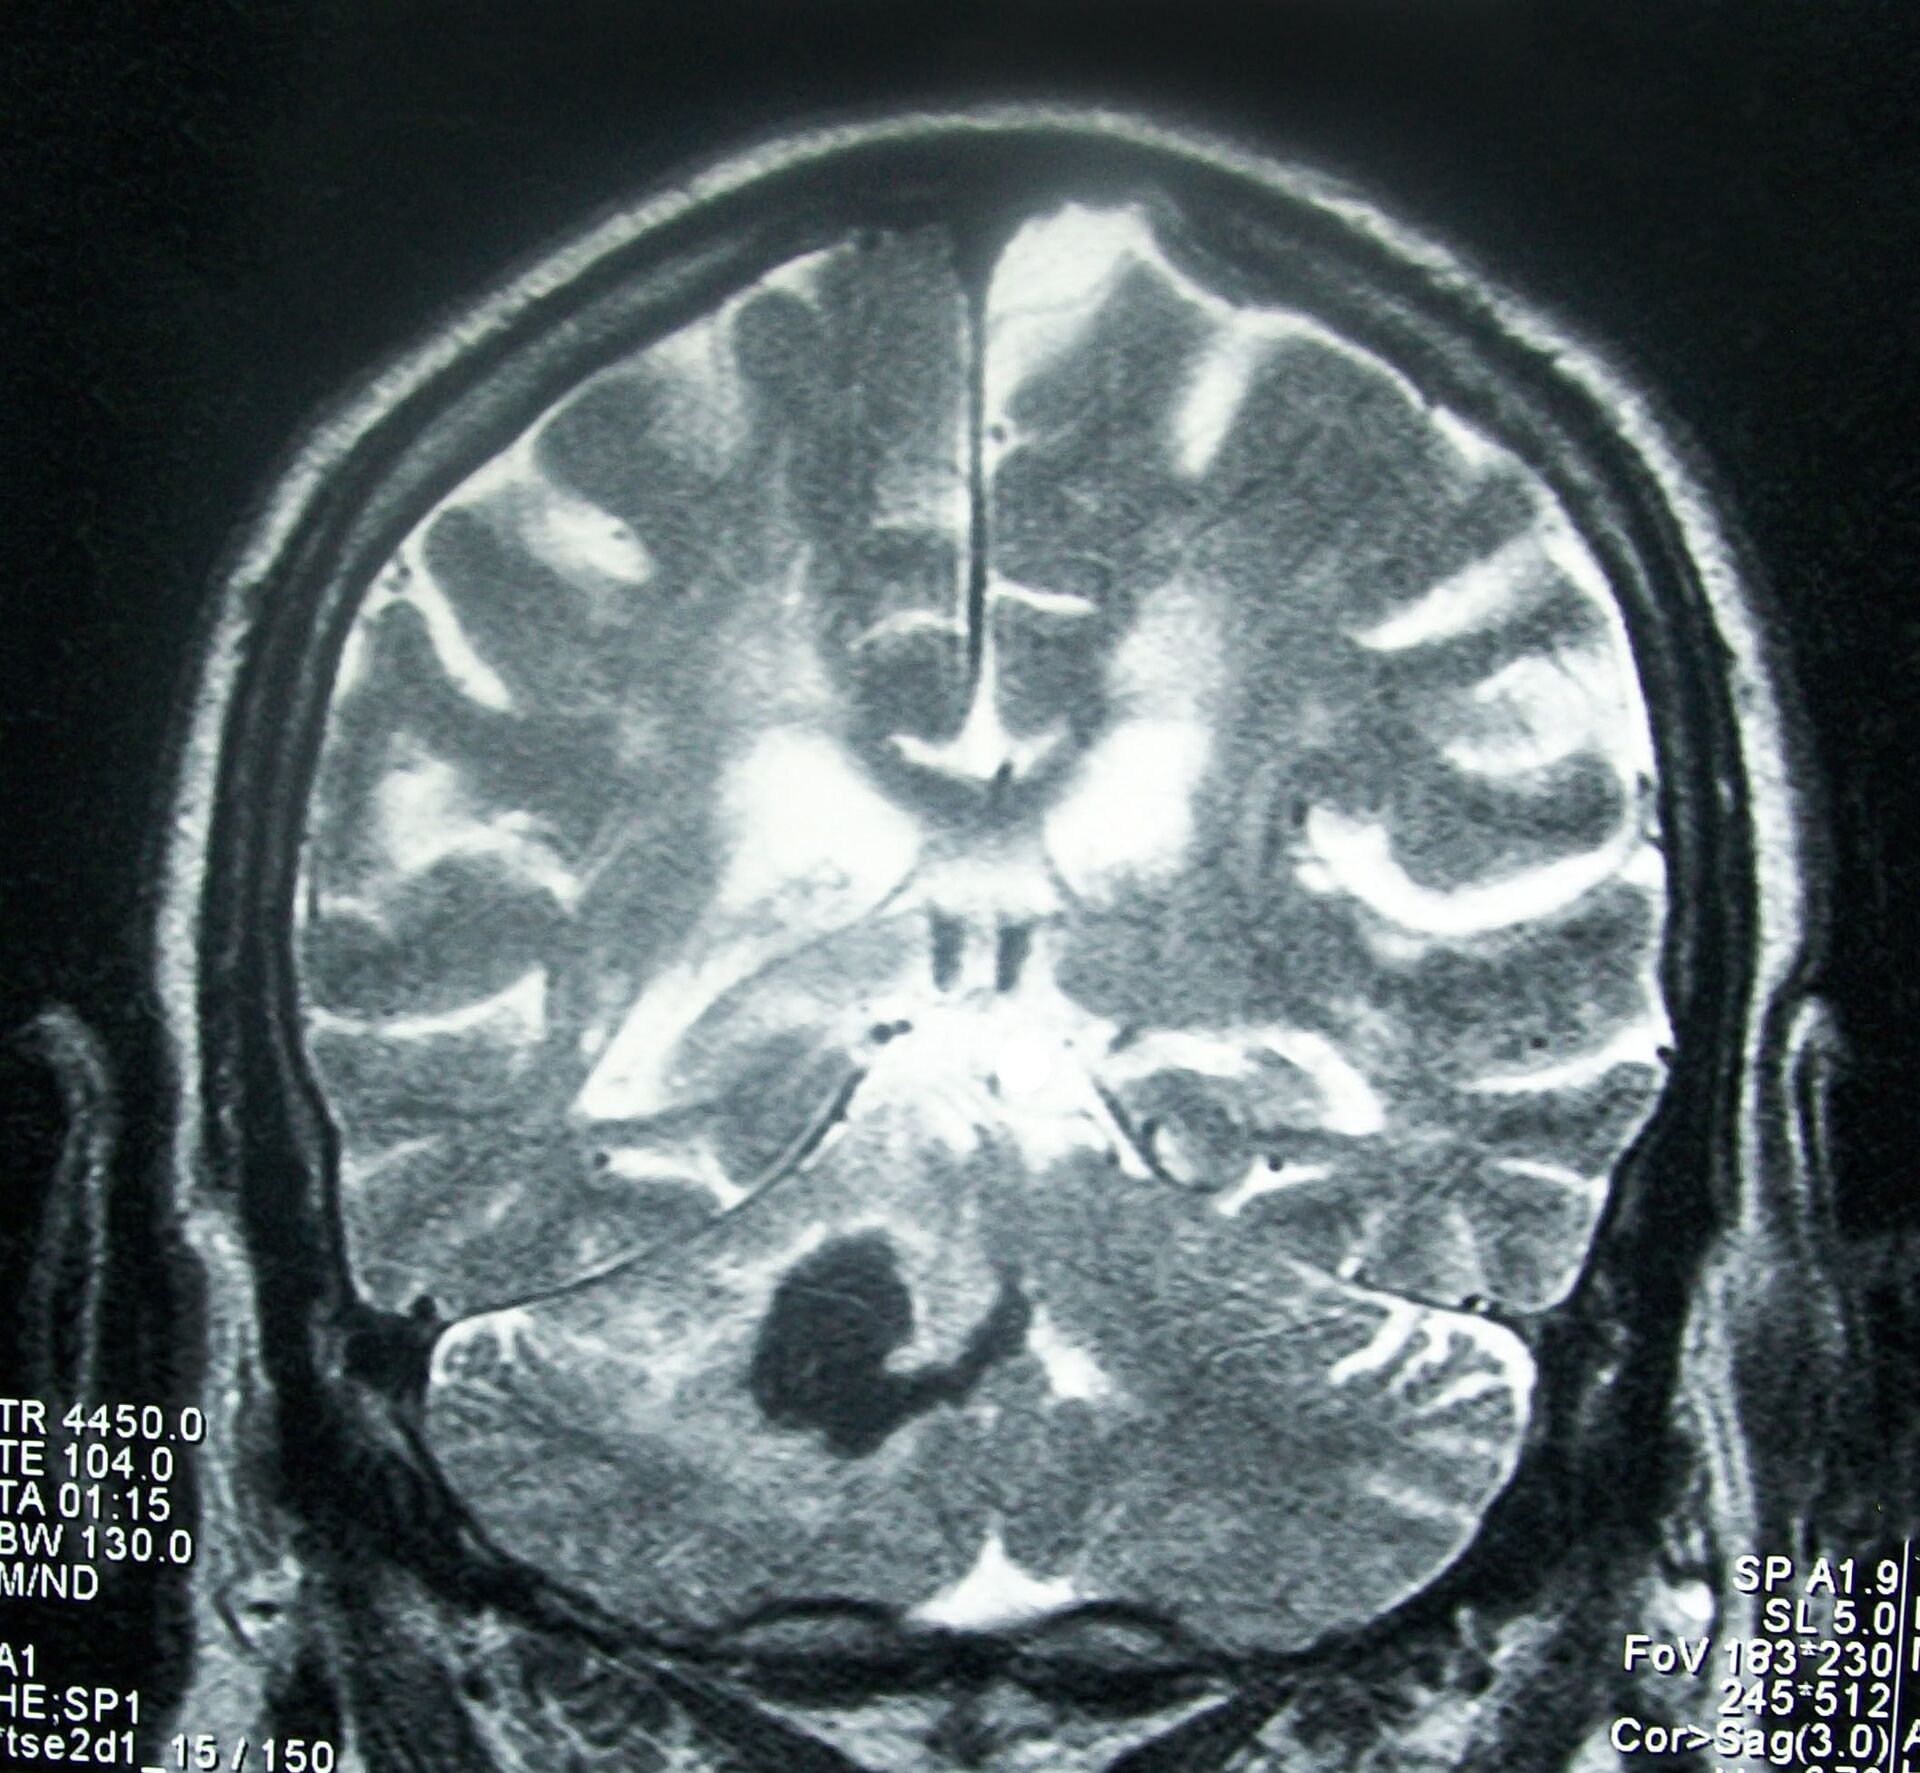

En una entrevista con el medio ruso AiF, la neuróloga

Aminat Dólova, del Centro Nacional del Cerebro y las Neurotecnologías, explicó que muchas personas no prestan la debida atención a la salud cerebral, aunque incluso los microderrames dan lugar a la formación de pequeñas zonas afectadas

en el cerebro que se ven claramente en las imágenes por resonancia magnética.